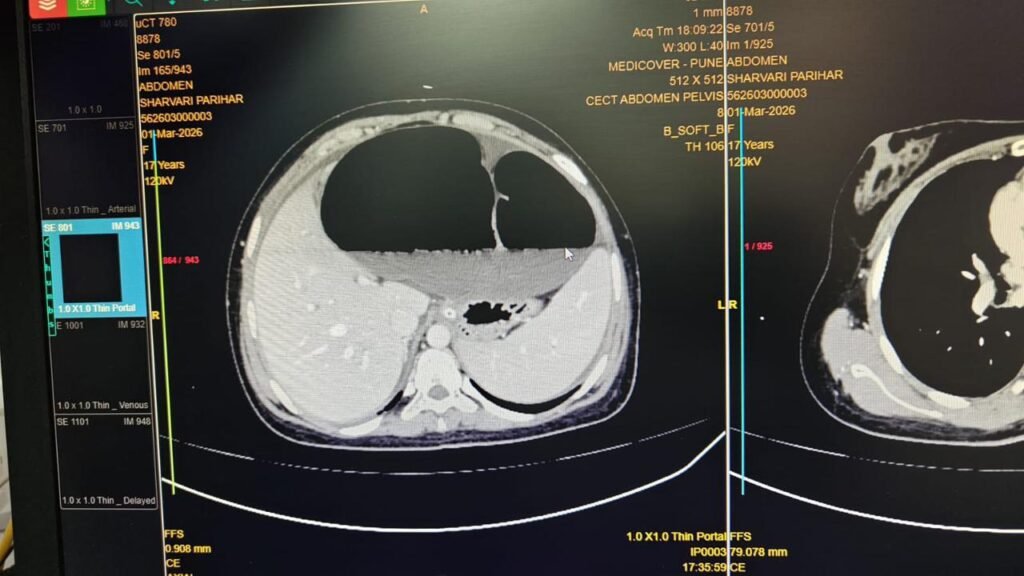

तपासणीदरम्यान मोठ्या आतड्यात अडथळा असल्याचा संशय व्यक्त करण्यात आला. पुढील तपासण्या, एक्स-रे आणि सीटी स्कॅनमध्ये सिग्मॉइड व्हॉल्व्युलस असल्याचे स्पष्ट झाले. या अवस्थेत सिग्मॉइड कोलन त्याच्या मेसेन्टरीभोवती १८० ते ३६० अंशांनी वळतो, ज्यामुळे आतड्यांमध्ये अडथळा निर्माण होतो आणि रक्तपुरवठाही धोक्यात येऊ शकतो.